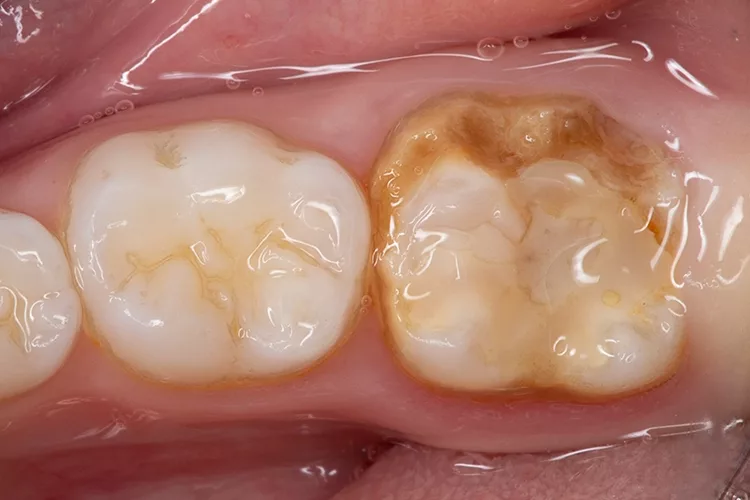

Eine Molaren-Inzisiven-Hypomineralisation (MIH) sollte in der Zahnarztpraxis frühzeitig erkannt werden, damit der betroffene junge Patient rasch versorgt, die Entwicklung seiner Zähne engmaschig überwacht und bei Bedarf schnell reagiert werden kann, um gravierende Folgen für Zahngesundheit und Lebensqualität des Kindes abzuwenden. Der folgende Beitrag legt den Fokus auf Therapiealternativen, die sich bei MIH unterschiedlichen Schweregrades bewährt haben.